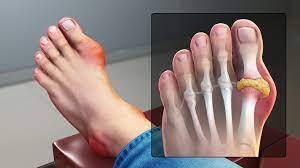

통풍의 정의

통풍은 높은 요산 농도로 인해 결정이 관절 주변에 쌓이면서 발생하는 만성적인 대사성 질환입니다. 이로 인해 관절과 주변 조직에 염증이 발생하며 통증, 부어오름, 열감 등의 증상이 나타날 수 있습니다. 주로 발 발가락의 관절에서 발생하지만 손, 발목, 무릎 등 다양한 관절에 영향을 미칠 수 있습니다. 통풍은 요산 결정이 관절 주변의 소프트 터치에 의해 활성화되거나 특정 상황에서 급작스럽게 악화될 수 있는 특징이 있습니다. 심각한 경우에는 관절 손상을 초래하여 일상생활에 큰 불편을 초래할 수 있습니다. 요산 결정의 쌓임을 예방하고 염증을 관리하는 것이 통풍 관리의 핵심입니다.